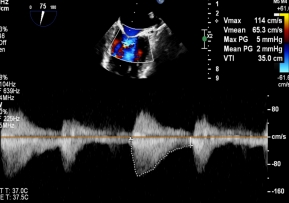

针对该病例特点,团队制定个体化诊疗策略,在穿刺位置、器械路径及夹持方式上进行精细设计。术中,团队优化房间隔穿刺高度与位置,匹配GAP结构特点;反复调整导向系统,确保器械垂直对准反流中心;通过多平面及三维TEE确认最佳夹持窗口;采用分步夹持策略,提高瓣叶抓取成功率,确保手术过程平稳。

【图片7-9:术中定位、夹持过程及术后效果图】

术后评估显示,患者二尖瓣反流由极重度明显降低至中度以下,血流动力学改善,手术取得良好效果